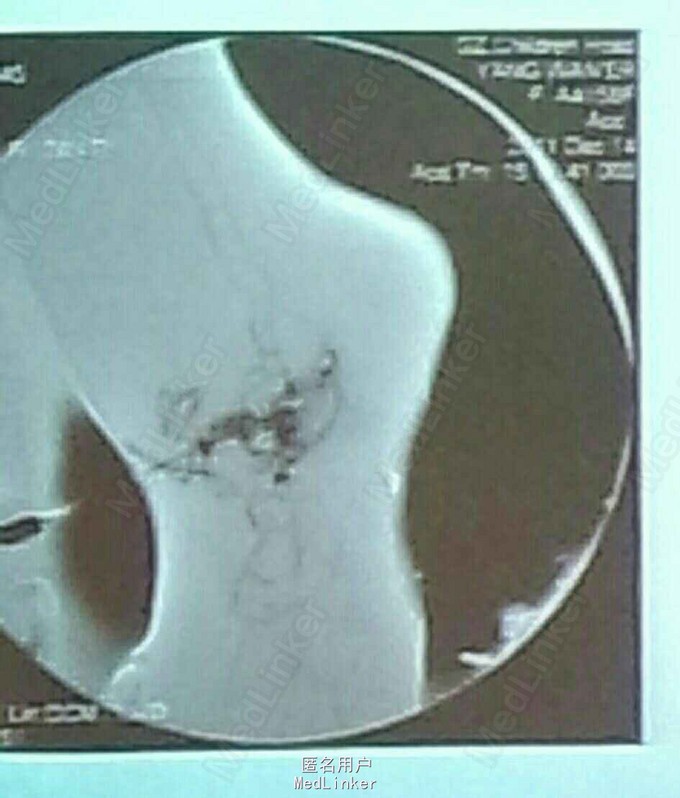

诊断:足部动静脉畸形 治疗:介入下造影,明确后于畸形处注射外科胶。再次造影动静脉畸形处未见造影剂。

儿童介入治疗常见于先心,但是动静脉畸形,血管瘤等方面也有用武之地。对于动静脉畸形介入治疗,使用弹簧圈还是外科胶,不同门派尚有争议。